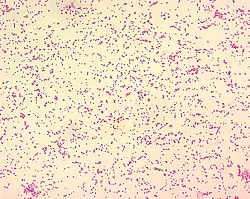

Bruceloza este o boală infecțioasă gravă produsă de speciile de Brucella, un gen de bacterii Gram-negative, aerobe, capsulate, care apar la microscop sub formă de bastonașe sau coci (cocobacili). Agentul patogen a fost izolat de medicul militar David Bruce în anul 1887 de la soldații bolnavi.